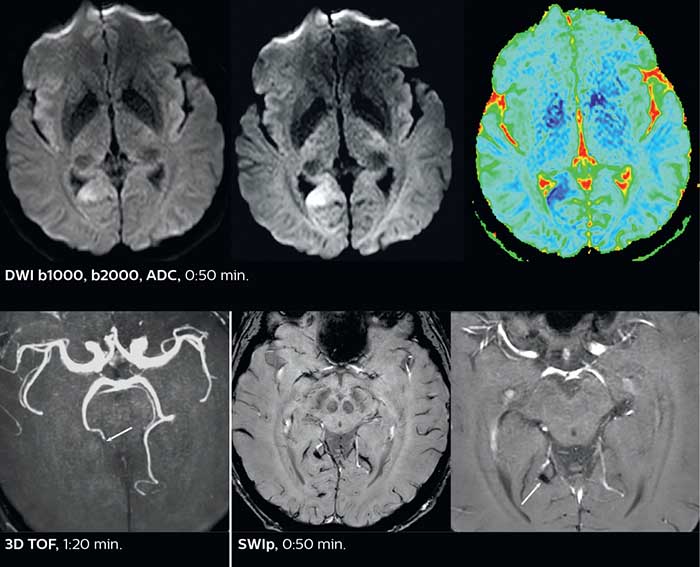

Performing advanced techniques has a direct impact on hospitalizations

So, what is the actual impact of having more information and more diagnostic confidence? According to Dr. Savatovsky, “One of the indications I’ve seen where using Elition is most impactful is in patients with suspected giant cell arteritis. As an ophthalmologic hospital, we see many patients with suspected giant cell arteritis. Usually we were performing MRI to help us rule out an ischemic stroke, and to verify that the supra aortic vessels are undamaged. With Elition, we still do this, but now we can add on more detailed high-resolution black-blood sequences on superficial arteries. This provides us with high confidence levels for diagnosis of giant cell arteritis (GCA) and as a result, some patients are not sent for a biopsy anymore. A patient who has a normal MRI will not require a biopsy and can be discharged from the hospital in the same day. Before, such a patient would have to stay for about a week, just to find that their biopsy results were negative. We have at least three or four patients a week with suspected giant cell arteritis. For a great deal of these patients we can have a direct impact on their hospital stay.”

Giant cell arteritis

The 3D TSE T1w black blood MSDE sequence with fat suppression has an isotropic 0.8 mm voxel size and sagittal oblique and axial reformats are made. The images show superficial temporal artery thickening and peri-arterial fat infiltration. The 3D TSE PDw black blood MSDE with fat suppression has 0.55 mm isotropic voxels. The images shows focal involvement of the frontal branch of the superficial temporal artery.